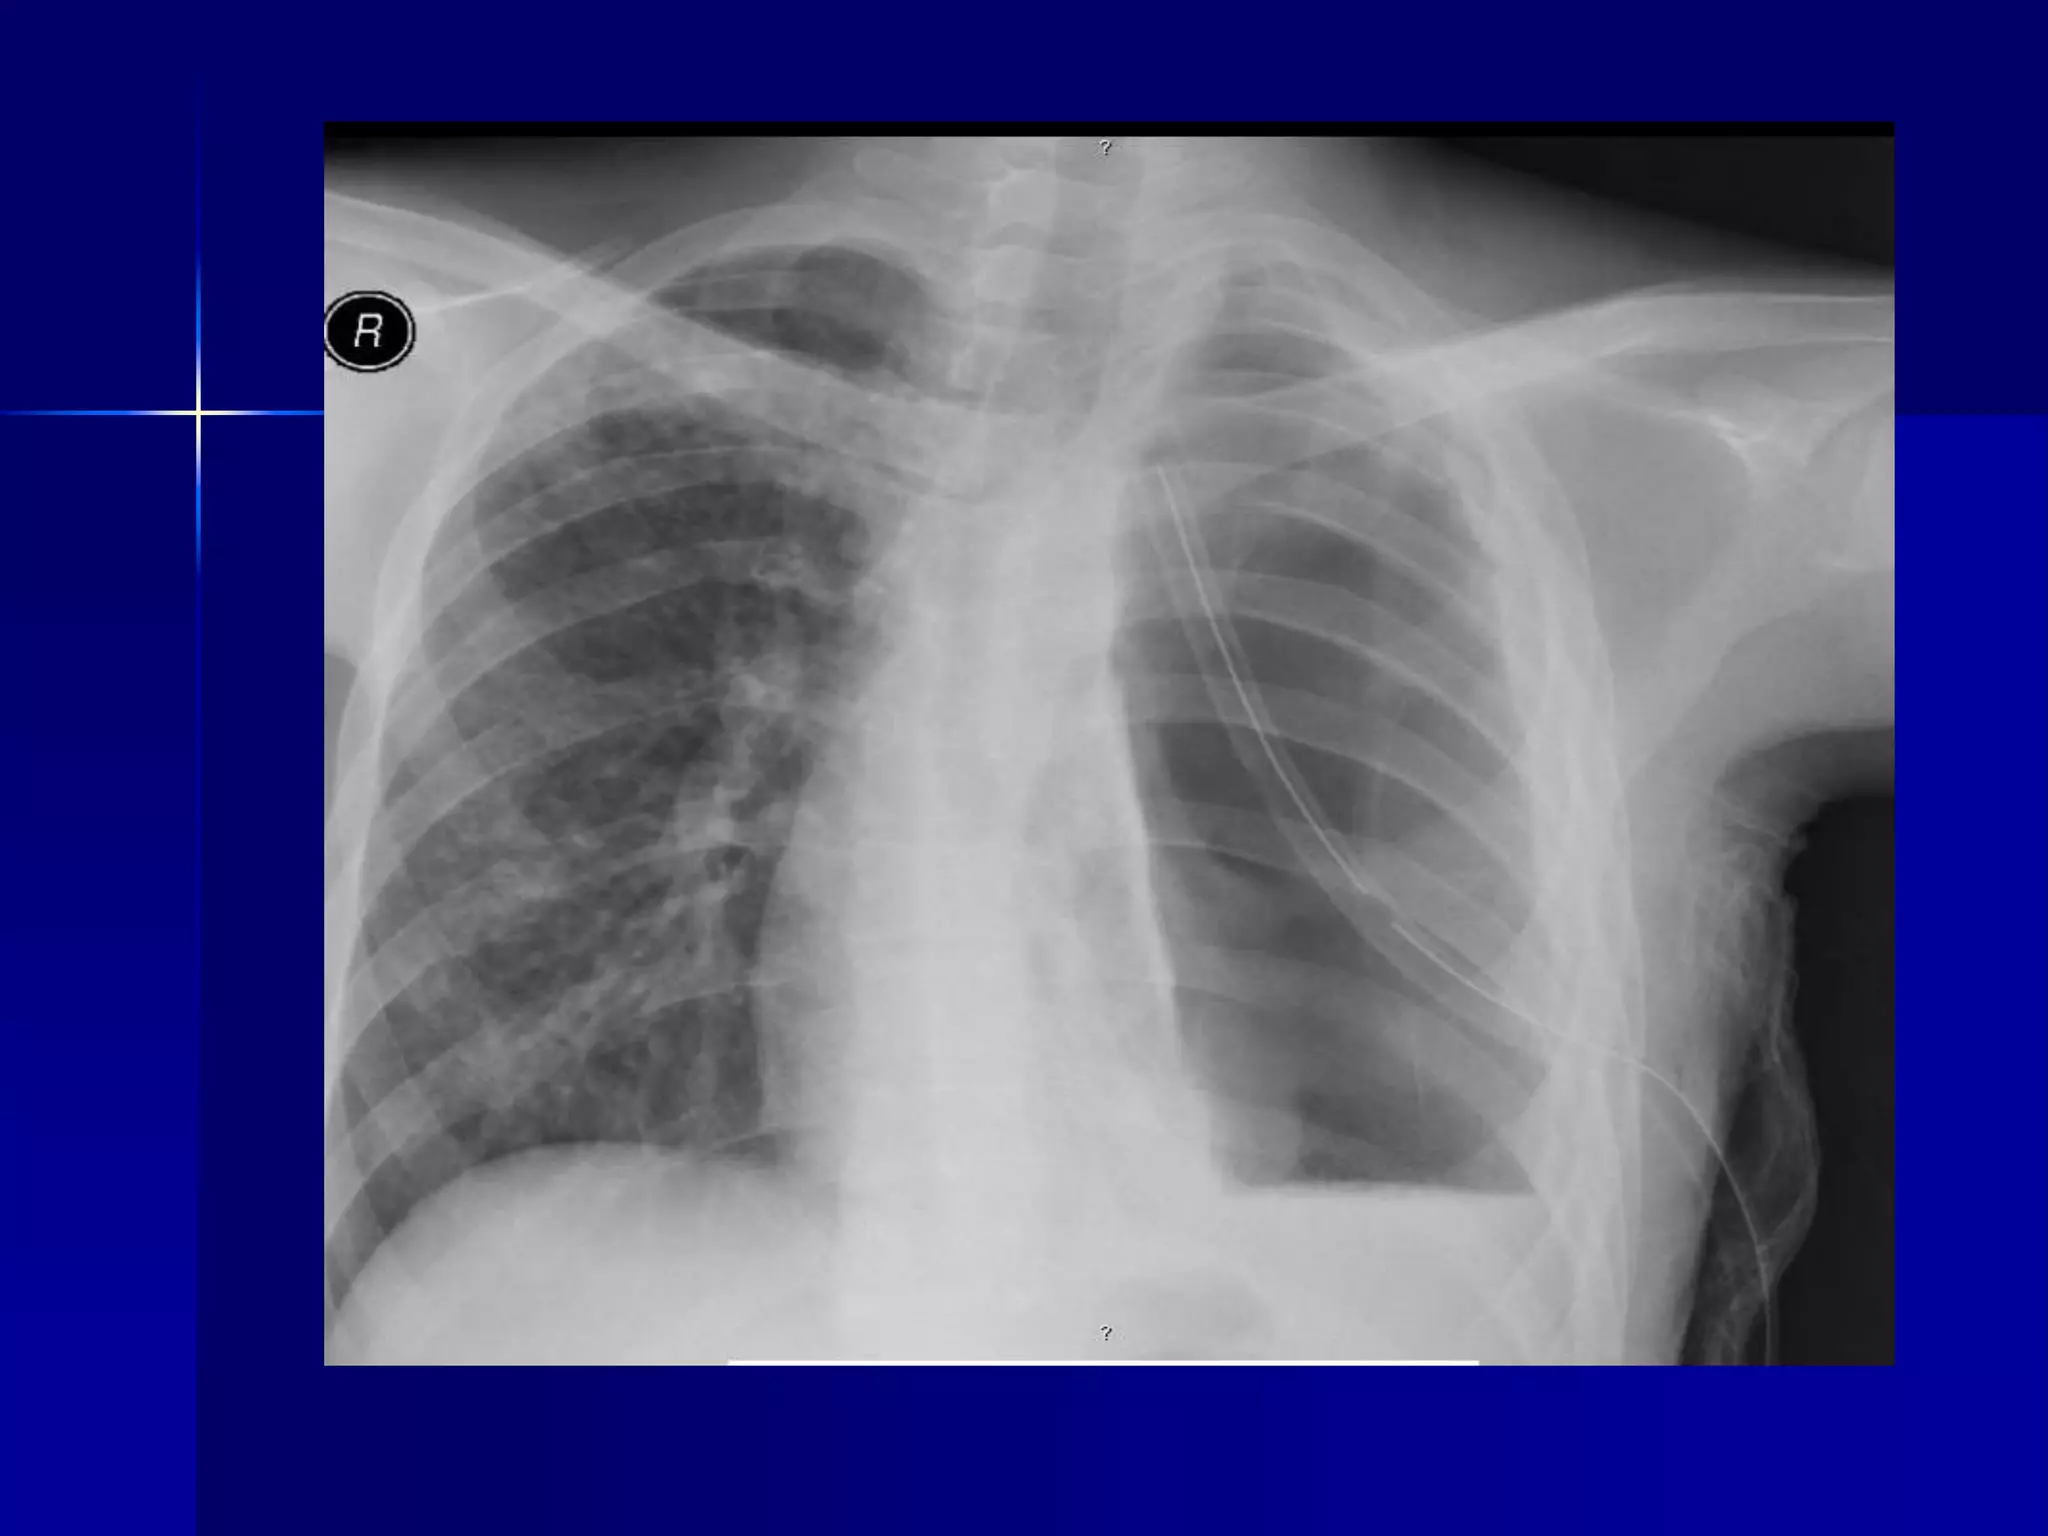

 Bronchiectasis

 Multiple bilateral basal air fluid levels

 Pleural Effusion

 Rheumatoid Arthritis

 Chest lateral and hand x-rays.